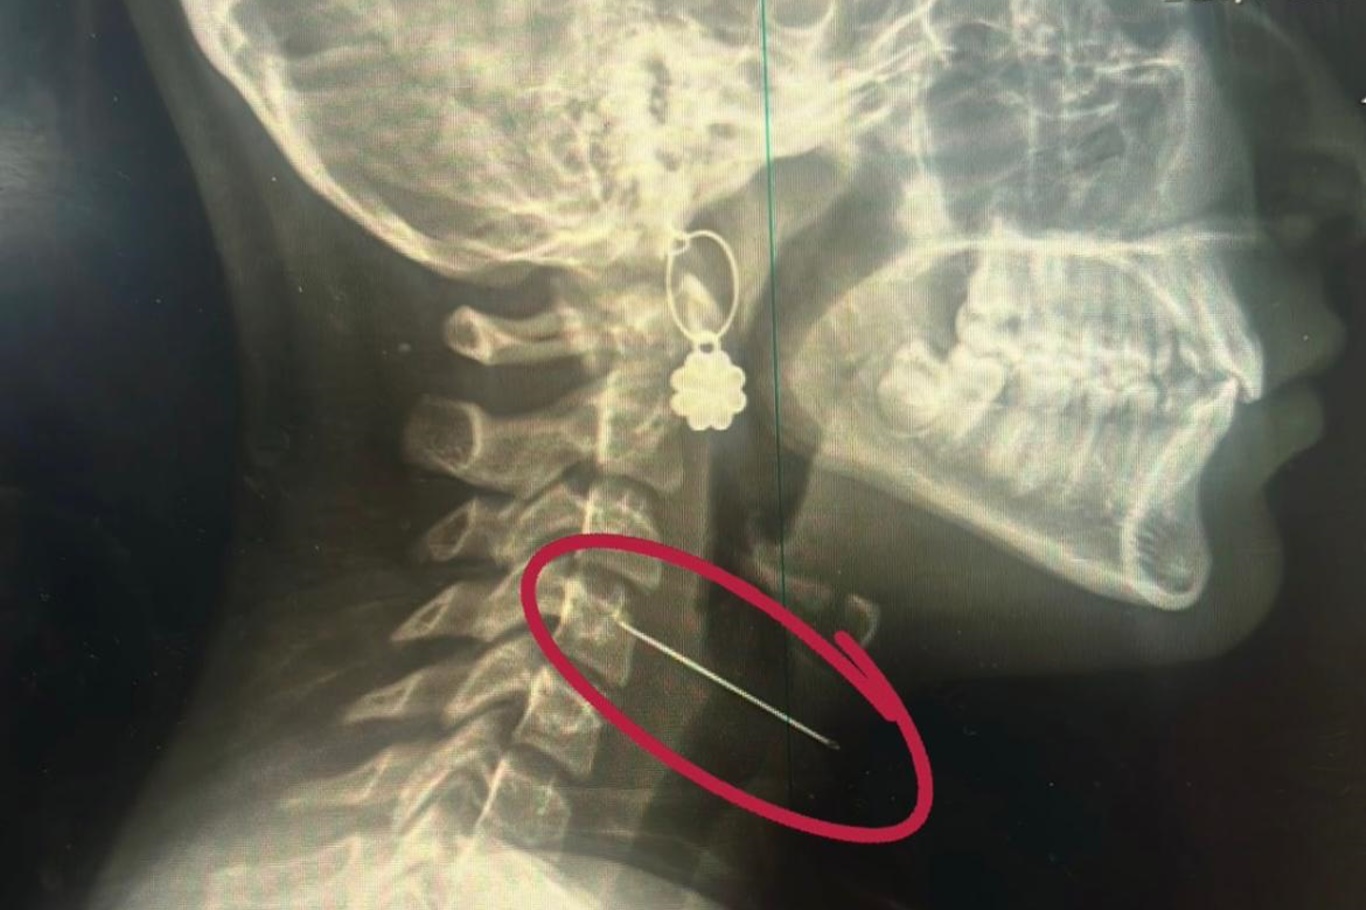

Çocuklarda sık karşılaşılan risklere değinen Özkaya "Günlük hayatta çocuklarda sık karşılaşılan yabancı cisim yutulması, kimyasal madde içilmesi ve solunum yollarına yabancı cisim kaçması önemli sağlık sorunları arasında yer almaktadır. Özellikle ilk üç yaşındaki çocuklar, yerde buldukları nesneleri ağızlarına götürme eğilimindedir. Madeni paralar, disk piller, iğneler ve küçük oyuncak parçaları çocuklar tarafından yutulabilmekte; bu maddeler yemek borusuna ya da solunum yollarına kaçabilmektedir. Bu tür durumlarda ailelerin olaya şahit olmaları hâlinde çocuğun ağzını kontrol etmeleri, yutma şüphesi varsa vakit kaybetmeden en yakın sağlık kuruluşuna başvurmaları gerekmektedir." dedi.

Solunum yollarına yabancı cisim kaçmasının da önemli bir risk olduğuna dikkat çeken Özkaya "Solunum yollarına yabancı cisim kaçması da günlük hayatta sık karşılaşılan ve hayati tehlike oluşturabilen durumlardan biridir. Özellikle üç yaşına kadar olan çocuklara çerez, fındık, fıstık, çekirdek gibi sert gıdaların verilmemesi gerekmektedir. Bu gıdalar solunum yollarına kaçarak ciddi nefes darlığına neden olabilmektedir. Böyle bir durumla karşılaşıldığında, mümkünse Heimlich manevrası uygulanmalı ve 112 Acil Servis eşliğinde en yakın sağlık kuruluşuna başvurulmalıdır. Bu tür vakaların operasyon gerektirebileceğine dikkat çekilerek, özellikle yemek borusunda kalan disk pillerin son derece tehlikeli olduğu vurgulanmaktadır. Disk piller, çocukta belirgin bir şikâyet olmasa bile kısa sürede yemek borusunda yanıklara ve delinmelere yol açabilmekte, hayati risk oluşturabilmektedir. Bu nedenle acil olarak ameliyathane ortamında çıkarılmaları gerekmektedir." şeklinde konuştu.